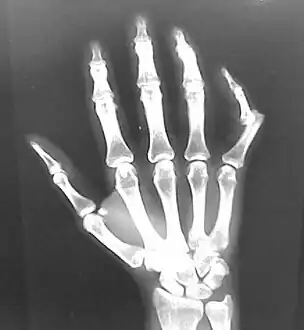

Dislocation of the carpo-metacarpal joint.

Radiograph of right fifth phalanx dislocation resulting from bicycle accident

Right fifth phalanx dislocation resulting from bicycle accident